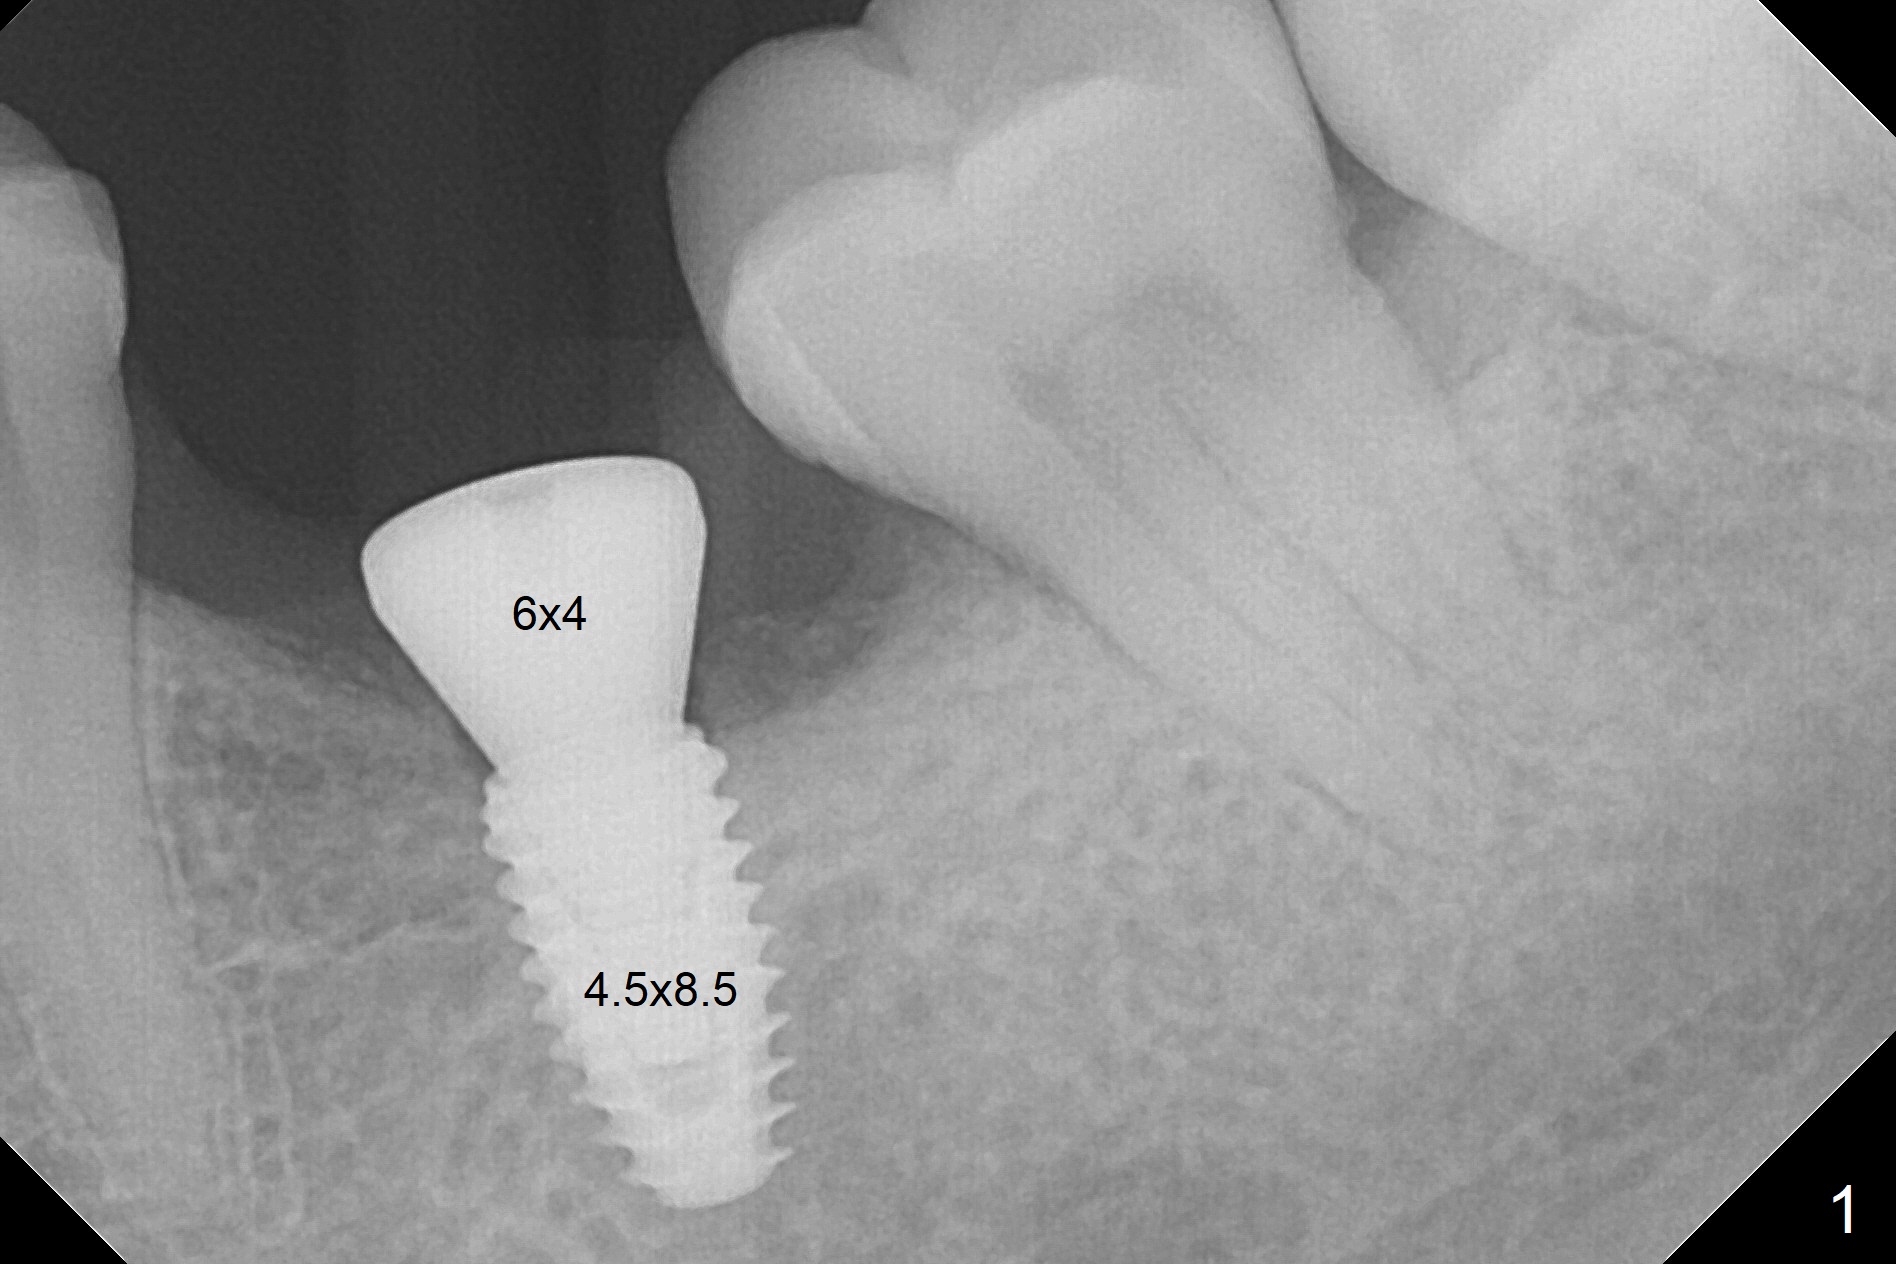

With 34 mg of Lidocaine and 17 mcg of Epinephrine (local infiltration), a 4.5x8.5 mm implant is placed with guide. The insertion torque is ~50 Ncm. It is placed in precise depth and in a short period of time (tolerable to the operators and patient, easier than mini-implant placement, Fig.1). There is no postop pain or paresthesia. The mesidistal position is within treatment plan (Fig.2). Miniimplants are placed to intrude #14 14 days prior. The teeth #16,17 and 32 are extracted 3 months postop. Minimal bone resorption at the crest is noted nearly 4 months postop (Fig.3). Bands and brackets are placed #18 upright 4 months postop (Fig.4 (14 niti wire)). The buccal and lingual view of the preop model shows that the supraerupted 1st molar (#14) has close relationship with the distal surface of the tooth #20 (Fig.5,6), accounting for the severe wear of the latter (Fig.8-11). The implant not only acts as an anchor to upright #18 in 4.5 months post banding (Fig.7 *), but also as an occlusal stop so that #18 has no interference to be moved. The stress on the implant results in radiating trabecular pattern (Fig.7,11 (9,11 months postop), as compared to before loading (Fig.1,3)). Restoring the distal contour of #20 with composite (Fig.12 C) makes it easy to close the space by adding porcelain the mesial surface of the implant crown. The crown/abutment is loose in China 7 months post cementation.